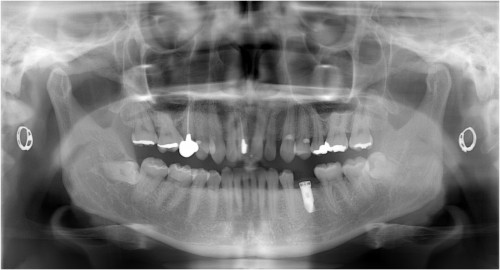

術前

抜歯後

埋入前(抜歯後約6ケ月)

上記、拡大写真

インプラント埋入直前

インプラント埋入時

同拡大

支台装着

被せ物装着

同全体写真